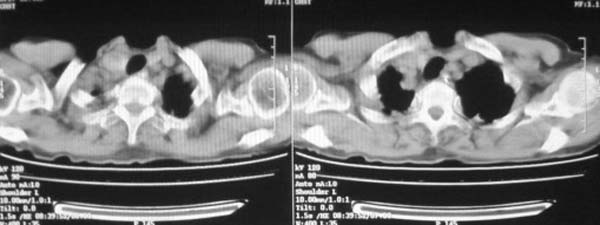

女,78岁,声嘶月余,否认有既往病史,有粉尘接触史10年。

颈部见多枚淋巴结肿大,考虑尘肺继发结核,喉部淋巴结钙化,不除外喉部慢性淋巴结炎、喉淀粉样变及类癌等

颈部多个肿大淋巴结,考虑矽肺并结核

符合矽肺,另外甲状腺可见病变,需强化明确.

考虑尘肺继发结核,喉部淋巴结钙化,不除外喉部慢性淋巴结炎。